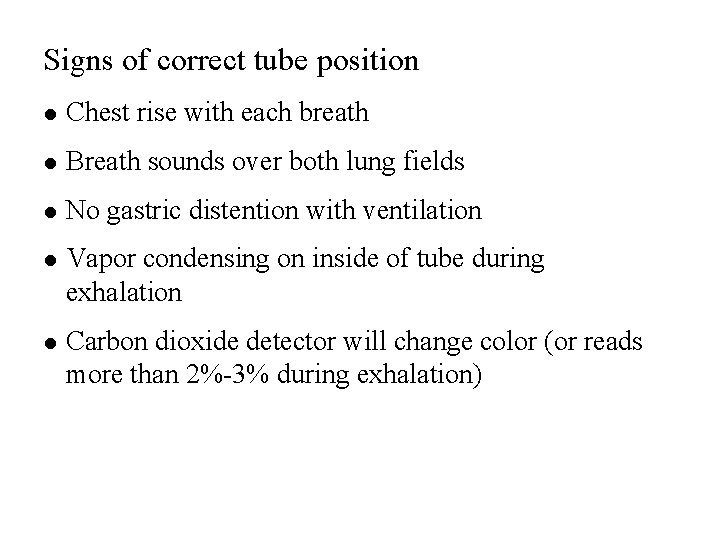

Signs of correct tube position l Chest rise with each breath l Breath sounds over both lung fields l No gastric distention with ventilation l Vapor condensing on inside of tube during exhalation l Carbon dioxide detector will change color (or reads more than 2%-3% during exhalation)